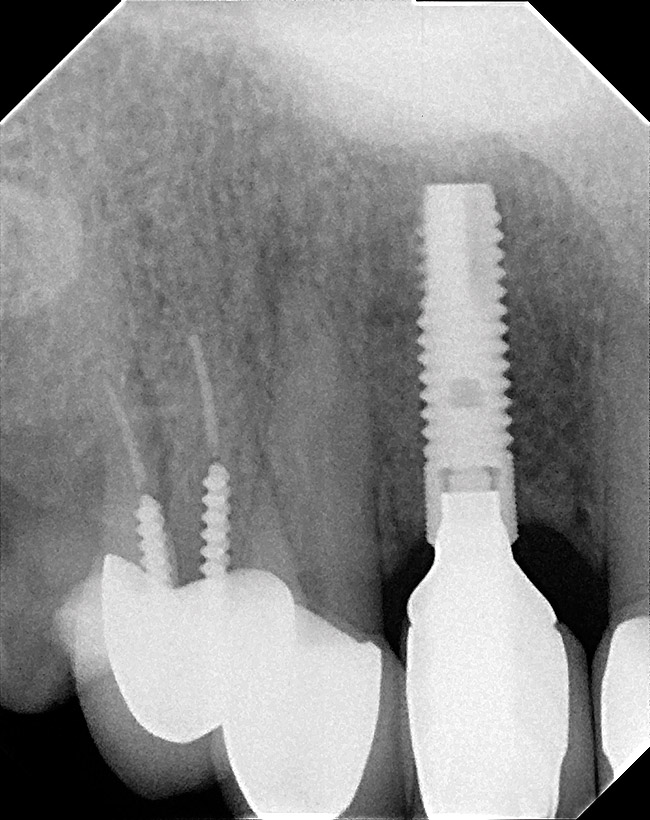

Figure 23  (Case 2) Radiograph at 24 months post loading.

Figure 23